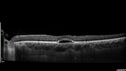

30 year old man The patient has always needed glasses and he goes to yearly appointments. The last time that he went there was some concern about the eyes. Everybody in his family has eye problems and uses glasses he is not sure if they see normally. PMhx: Anxiety, Depression Meds: MELOXICAM. LORAZEPAM. methcarbonale VA OD: Dcc20/40 VA OS: Dcc20/20-2 IOP: TP: OD:9 OS:12

Best Disease221 views30 year old man vision 20/40 OD, 20/20 OS - strong family history00000